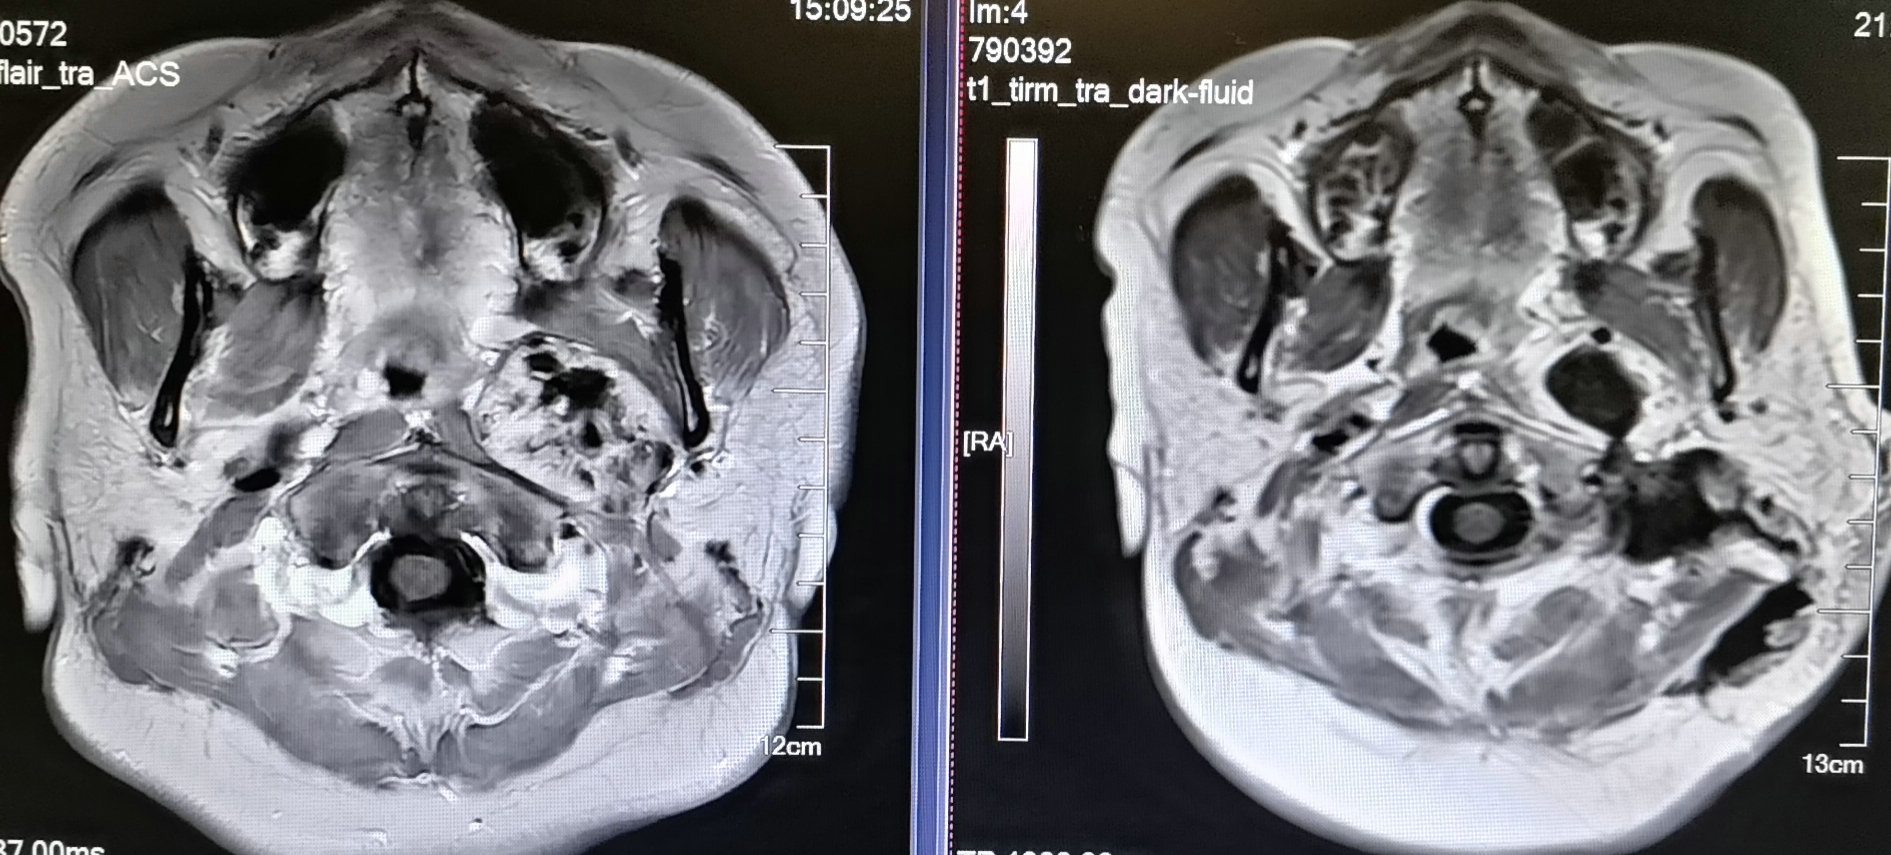

术前磁共振